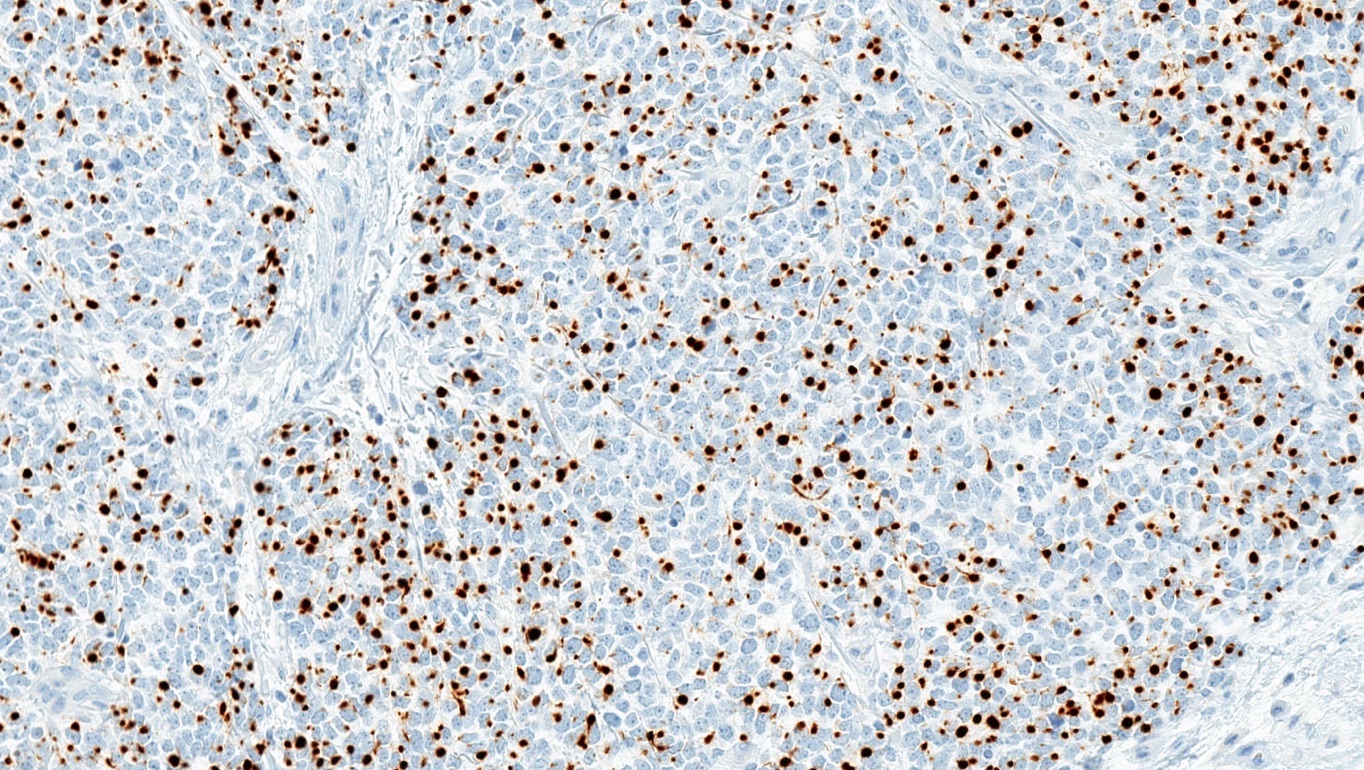

Microscopic (histologic) images

Positive stains

- Broad spectrum keratins: CAM 5.2, AE1 / AE3 (paranuclear, cytoplasmic or mixed pattern)

- CK20 (classic dot-like paranuclear pattern)

- Chromogranin, synaptophysin, CD56, neuron specific enolase

- Neurofilament (dot-like pattern)

- Variable MCPyV (nuclear pattern)